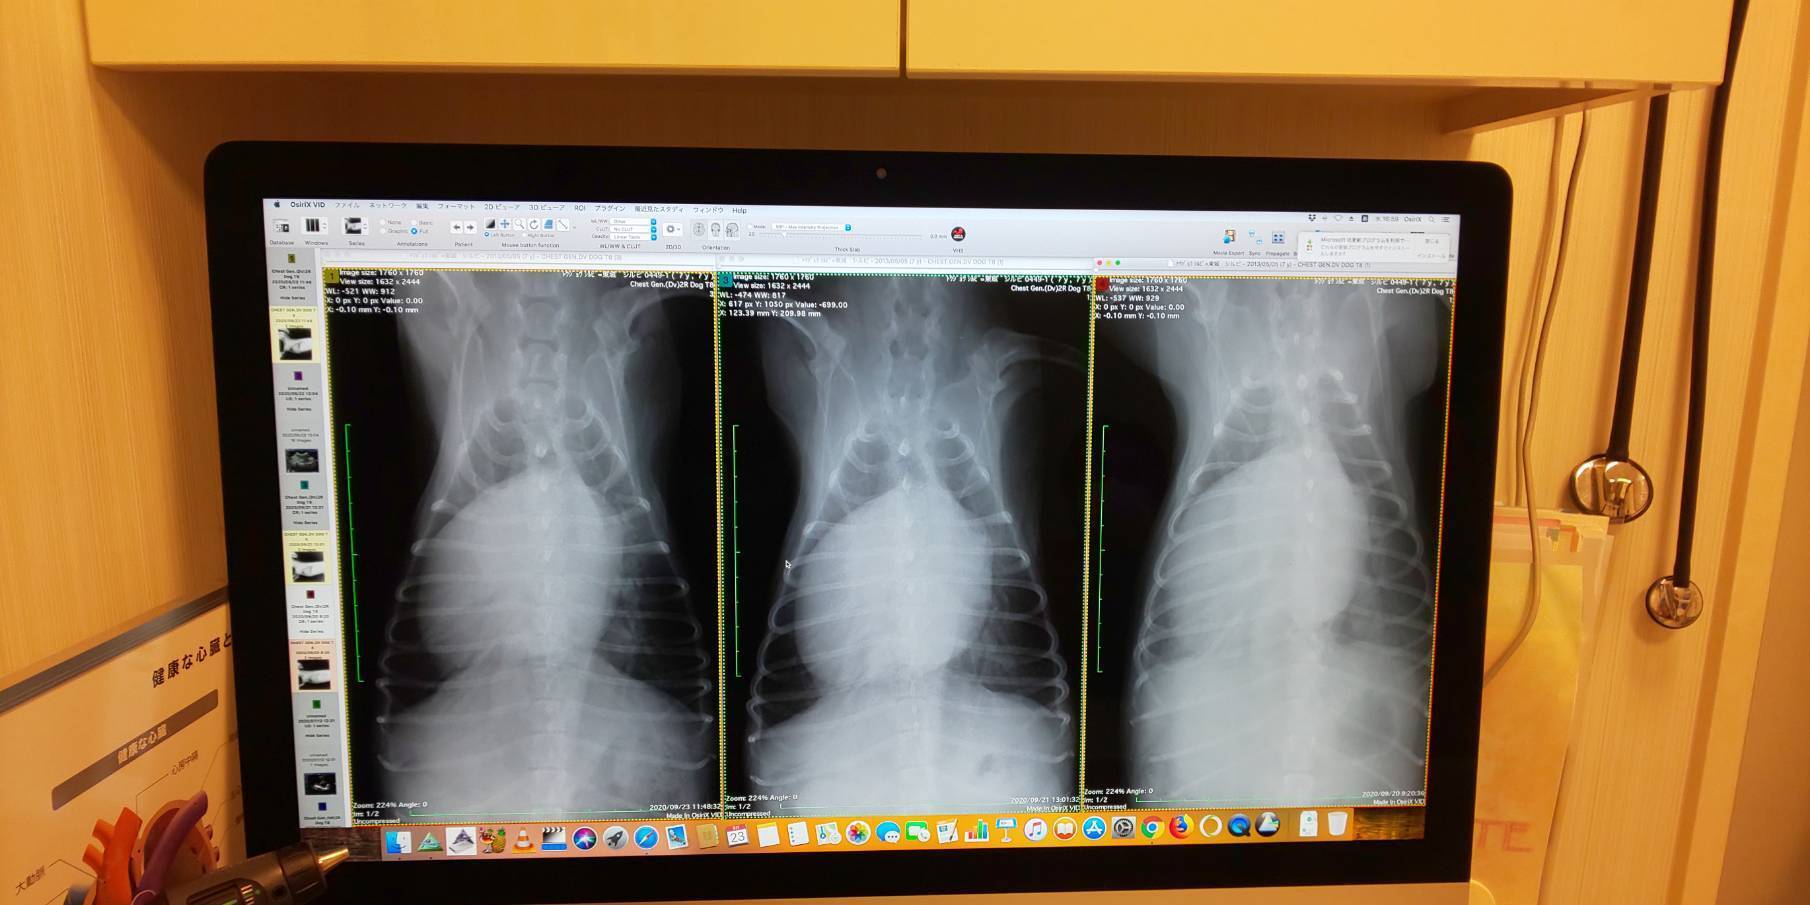

上からのレントゲン右から白い影が消えてくのが分かります。真ん中の白いのが心臓です。左心房の肥大がこれでも分かります。本来は真ん中から右に広がってるぐらいが左にもあるんですが、左側はあばら骨に接するぐらい肥大してます。